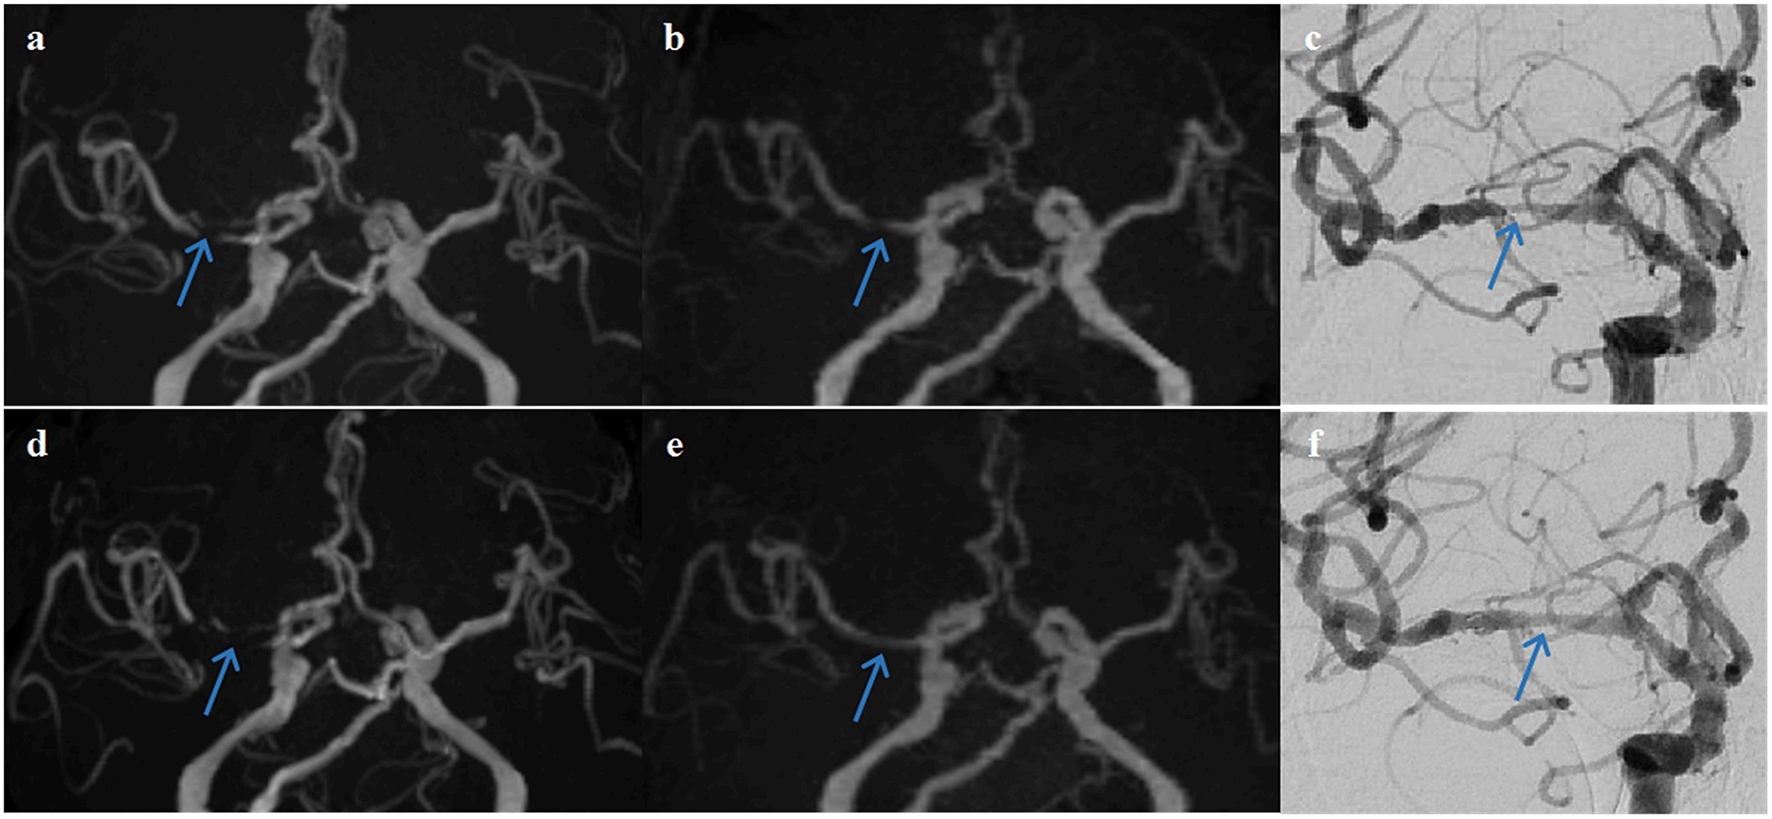

The examples from two patients having pre- and post-interventional imaging are shown in Figures 4, 5.

Figure 5

A representative case of a 68-year-old female patient who underwent stent angioplasty due to atherosclerotic stenosis of the right middle cerebral artery (MCA) at the M1 segment (blue arrows). Pre-intervention images are shown on the top row (a) TOF-MRA, (b) PETRA-MRA, and (c) DSA. The degree of stenosis was 100% on TOF (pseudo-occlusion), 79.8% on PETRA-MRA, and 86.3% on DSA. Image quality scores of the PETRA-MRA and 3D-TOF were 4 and 3, respectively. Post-intervention images are shown on the bottom row (d) 3D-TOF, (e) PETRA-MRA, and (f) DSA. Post-intervention TOF-MRA had strong signal loss near the stent, and post-intervention PETRA-MRA had minimal signal loss near the stent comparing with reference DSA. PETRA-MRA had significantly higher image quality scores than those of TOF-MRA considering flow visualization within the stents (PETRA-MRA, 4; 3D-TOF, 1) and susceptibility artifact (PETRA-MRA, 4; 3D-TOF, 1).